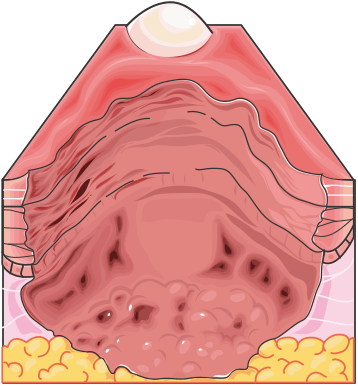

Third-Degree Burns: Also known as full-thickness burns, these injuries involve the complete destruction of the epidermis and dermis, extending into the subcutaneous tissue. The skin may appear charred. Third-degree burns are typically painless due to nerve destruction, and they require surgical intervention, such as debridement and skin grafting, for proper healing.

Figure 1.23, generated using Servier Medical Art, provided by Servier, licensed under a Creative Commons Attribution 4.0 unported license

Fourth-Degree Burns: These burns go beyond the skin, damaging underlying muscles, tendons, and bones. They are life-threatening and always require extensive surgical intervention.